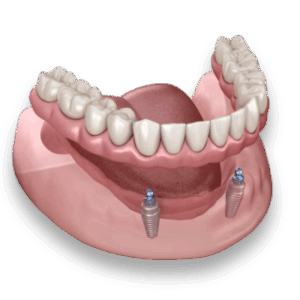

ایمپلنت دندانی متحرک چیست؟

ایمپلنتهای متحرک یا دنچر اسنپآن ترکیبی از دندان مصنوعی سنتی و ایمپلنت ثابت هستند. این نوع ایمپلنت به تراکم استخوان کمتری نیاز دارد و معمولاً برای طیف وسیعتری از بیماران مناسب است. یک مکانیزم اتصال ویژه باعث میشود بتوانید آن را به راحتی در دهان نصب یا خارج کنید.

دندانها معمولاً از آکریلیک ساخته میشوند و میتوان آنها را به سادگی برای تمیز کردن یا تنظیم، از دهان خارج کرد.

مزایا

- جراحی کمتر و بهبود سریعتر.

- امکان خارج کردن و شستوشوی آسان بدون نیاز به چسب.

- قابل تنظیم یا تعویض در صورت نیاز.

- مناسب برای افرادی با تراکم استخوان کمتر.

- هزینه معمولاً پایینتر از ایمپلنت ثابت.

- امکان خارج کردن بعد از غذا برای تمیز کردن کامل.

ایمپلنت متحرک:

- معاینه و برنامهریزی

- کاشت تعداد کمتری پایه فلزی

- دوره بهبودی کوتاهتر)معمولاً ۶ تا ۸ هفته (

- ساخت و نصب دنچر اسنپآن